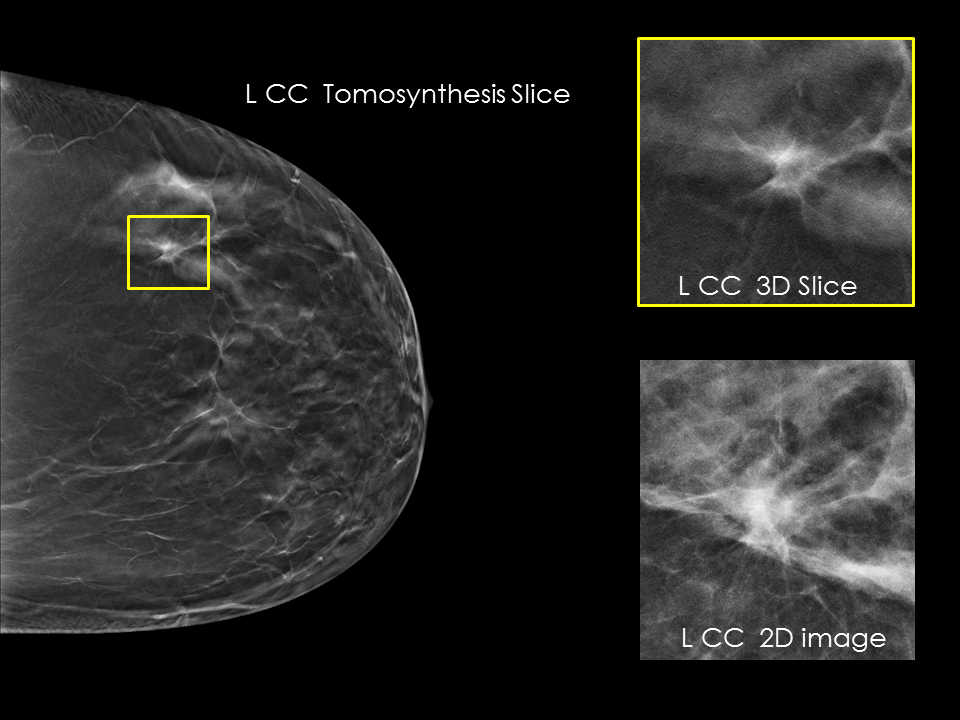

Better visibility

Designed to improve visibility of fine details for greater diagnostic confidence.*

* is compared to 2D alone